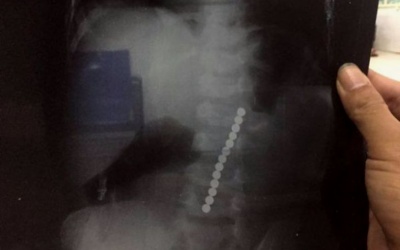

Khi bé Nguyễn Hữu T. (2 tuổi, Nghệ An) xuất hiện tình trạng nôn ói dữ dội, gia đình cho rằng bé bị ngộ độc thức ăn, đưa đi viện khám. Hình ảnh phim chụp X-quang phát hiện cả chuỗi hạt...